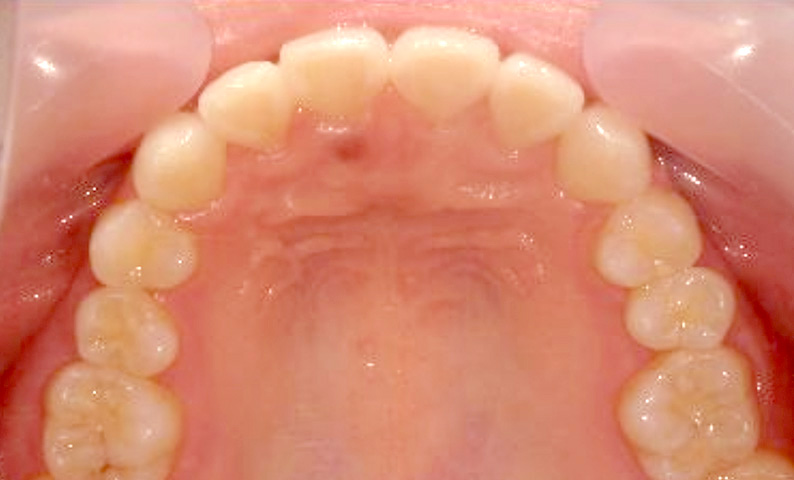

症例_025 上顎だけの部分矯正

治療期間:7ヶ月金額:30万円+税女性前歯のガタガタ上の前歯だけ

| Before | After |